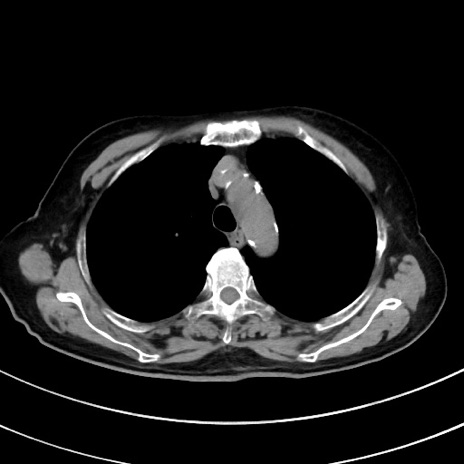

症例33(横断像)

【症例】70歳代 女性

【主訴】心窩部痛

【現病歴】延髄病変の精査・加療にて神経内科入院中。本日より心窩部痛あり。

【既往歴】虫垂炎

【身体所見】右下腹部を中心に圧痛と反跳痛あり。

【データ】WBC 10900、CRP 0.02